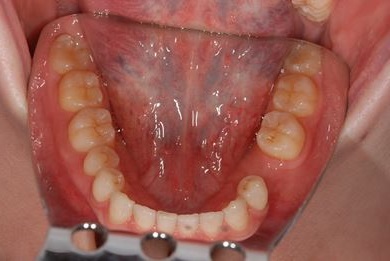

| 性別/年齢 | 女性 / 29歳 | ||||||||||||||||||||||||||||||||

| 主訴 | インプラント治療と、親知らずの抜歯の相談。なるべく安価で、短期間で終了して欲しい。 | ||||||||||||||||||||||||||||||||

| 治療方針 | 欠損部分をインプラント治療にて、機能的・審美的回復を行う。 | ||||||||||||||||||||||||||||||||

| 治療内容 | インプラント1本、メタルボンドセラミッククラウン1本 | ||||||||||||||||||||||||||||||||

| 総治療費 | 252,000円 | ||||||||||||||||||||||||||||||||

| 治療期間 | 11ヶ月 |